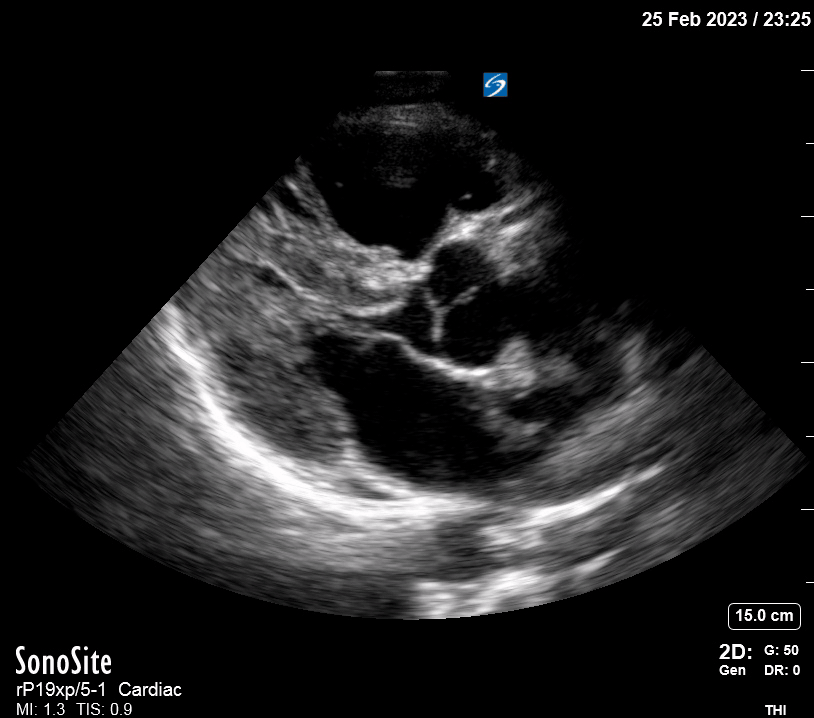

Equality: is the RV dilated or significantly impaired?

Normally, the RV is a low-pressure, thin-walled, high-compliance chamber that wraps anteriorly around the muscular, cone-shaped LV. The normal RV : LV diameter ratio is 0.6 : 1.

When the pulmonary artery pressure rises, the RV will dilate, altering the normal RV:LV ratio. Although sacrificing sensitivity, the use of equality (1:1 ratio) as a cutoff can achieve a specific estimation of RV strain. If imaged correctly by a trained operator, the presence of an RV:LV ratio > 1 is highly specific for RV strain.

RV dilation can be acute, chronic, or acute-on-chronic. However, in patients presenting with undifferentiated chest pain, shortness of breath, hypotension or syncope, the presence of any RV dilation should raise suspicion for acute pulmonary embolism (PE). Furthermore, in a patient in shock, the presence of RV strain may signal the need for aggressive therapy – emergency thrombolysis.

THE VIEWS

The A4C view provides an accurate chamber size comparison. However, achieving a proper A4C view (avoiding foreshortening or ballooning, and visualising the four chambers with a vertically oriented interventricular septum) can be a challenging exercise of image acquisition. Additionally, the PSAX view at the level of the papillary muscles shows both LV and RV side by side and is useful to assess function and size. When RV pressure is high, the septum will be pushed and flattened towards the LV, resulting in the characteristic “D-shaped” LV or “D sign”.